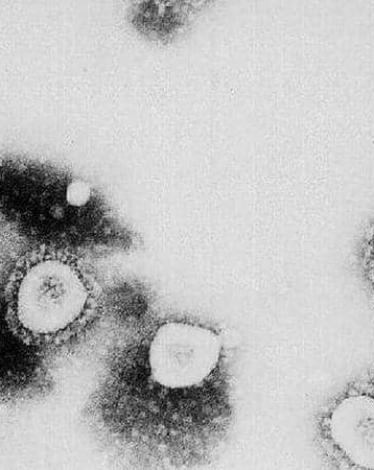

تحذيرات علمية من "مشروب كورونا".. فماذا تعرف عنه؟

ما الذي يجعل فيروس كورونا المستجد شديد العدوى؟

هل يمكن للأطفال نقل فيروس كورونا للبالغين؟

جديد العلماء: جسم مضاد يضرب "تاج" الفيروس ويخرب شكله

لهذا السبب .. فيروس كورونا أكثر فتكا بالذكور

رقاقة لاصقة لكشف الإصابة بـ"كورونا".. تعرّف عليها

بسبب حالة العدوى.. "عواقب خطيرة" تهدد مصابي كورونا

"تأثير غامض" لفيروس كورونا يحير الأطباء

لقاح كورونا.. بين تفاؤل ترامب وتشاؤم الألمان